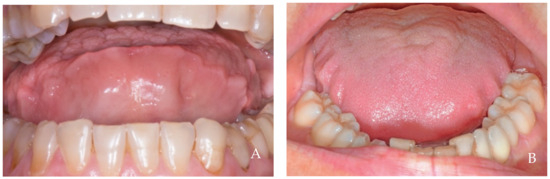

2. Clinical Examples of Oral Soft Tissue Growth